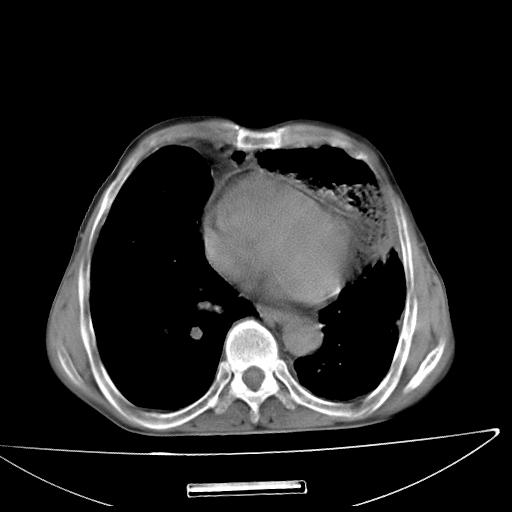

男  70岁,发烧咳嗽4天。盗汗,消瘦。无痰中带血丝,以前有肺tb病史,ct见,双肺tb,左侧胸廓塌陷,左胸膜肥厚粘连。纵隔移位,右侧胸腔积液,大家说说那个心影前左肺舌叶除了肺大炮还有炎症还是干酪性肺炎?有占位吗?我看纵隔淋巴结也大。

1)两肺继发性肺结核并左肺上叶肺不张,支气管扩张。2)双侧胸膜炎(胸膜增厚+少量胸腔积液)。

双肺继发性肺结核伴部分左肺毁损。